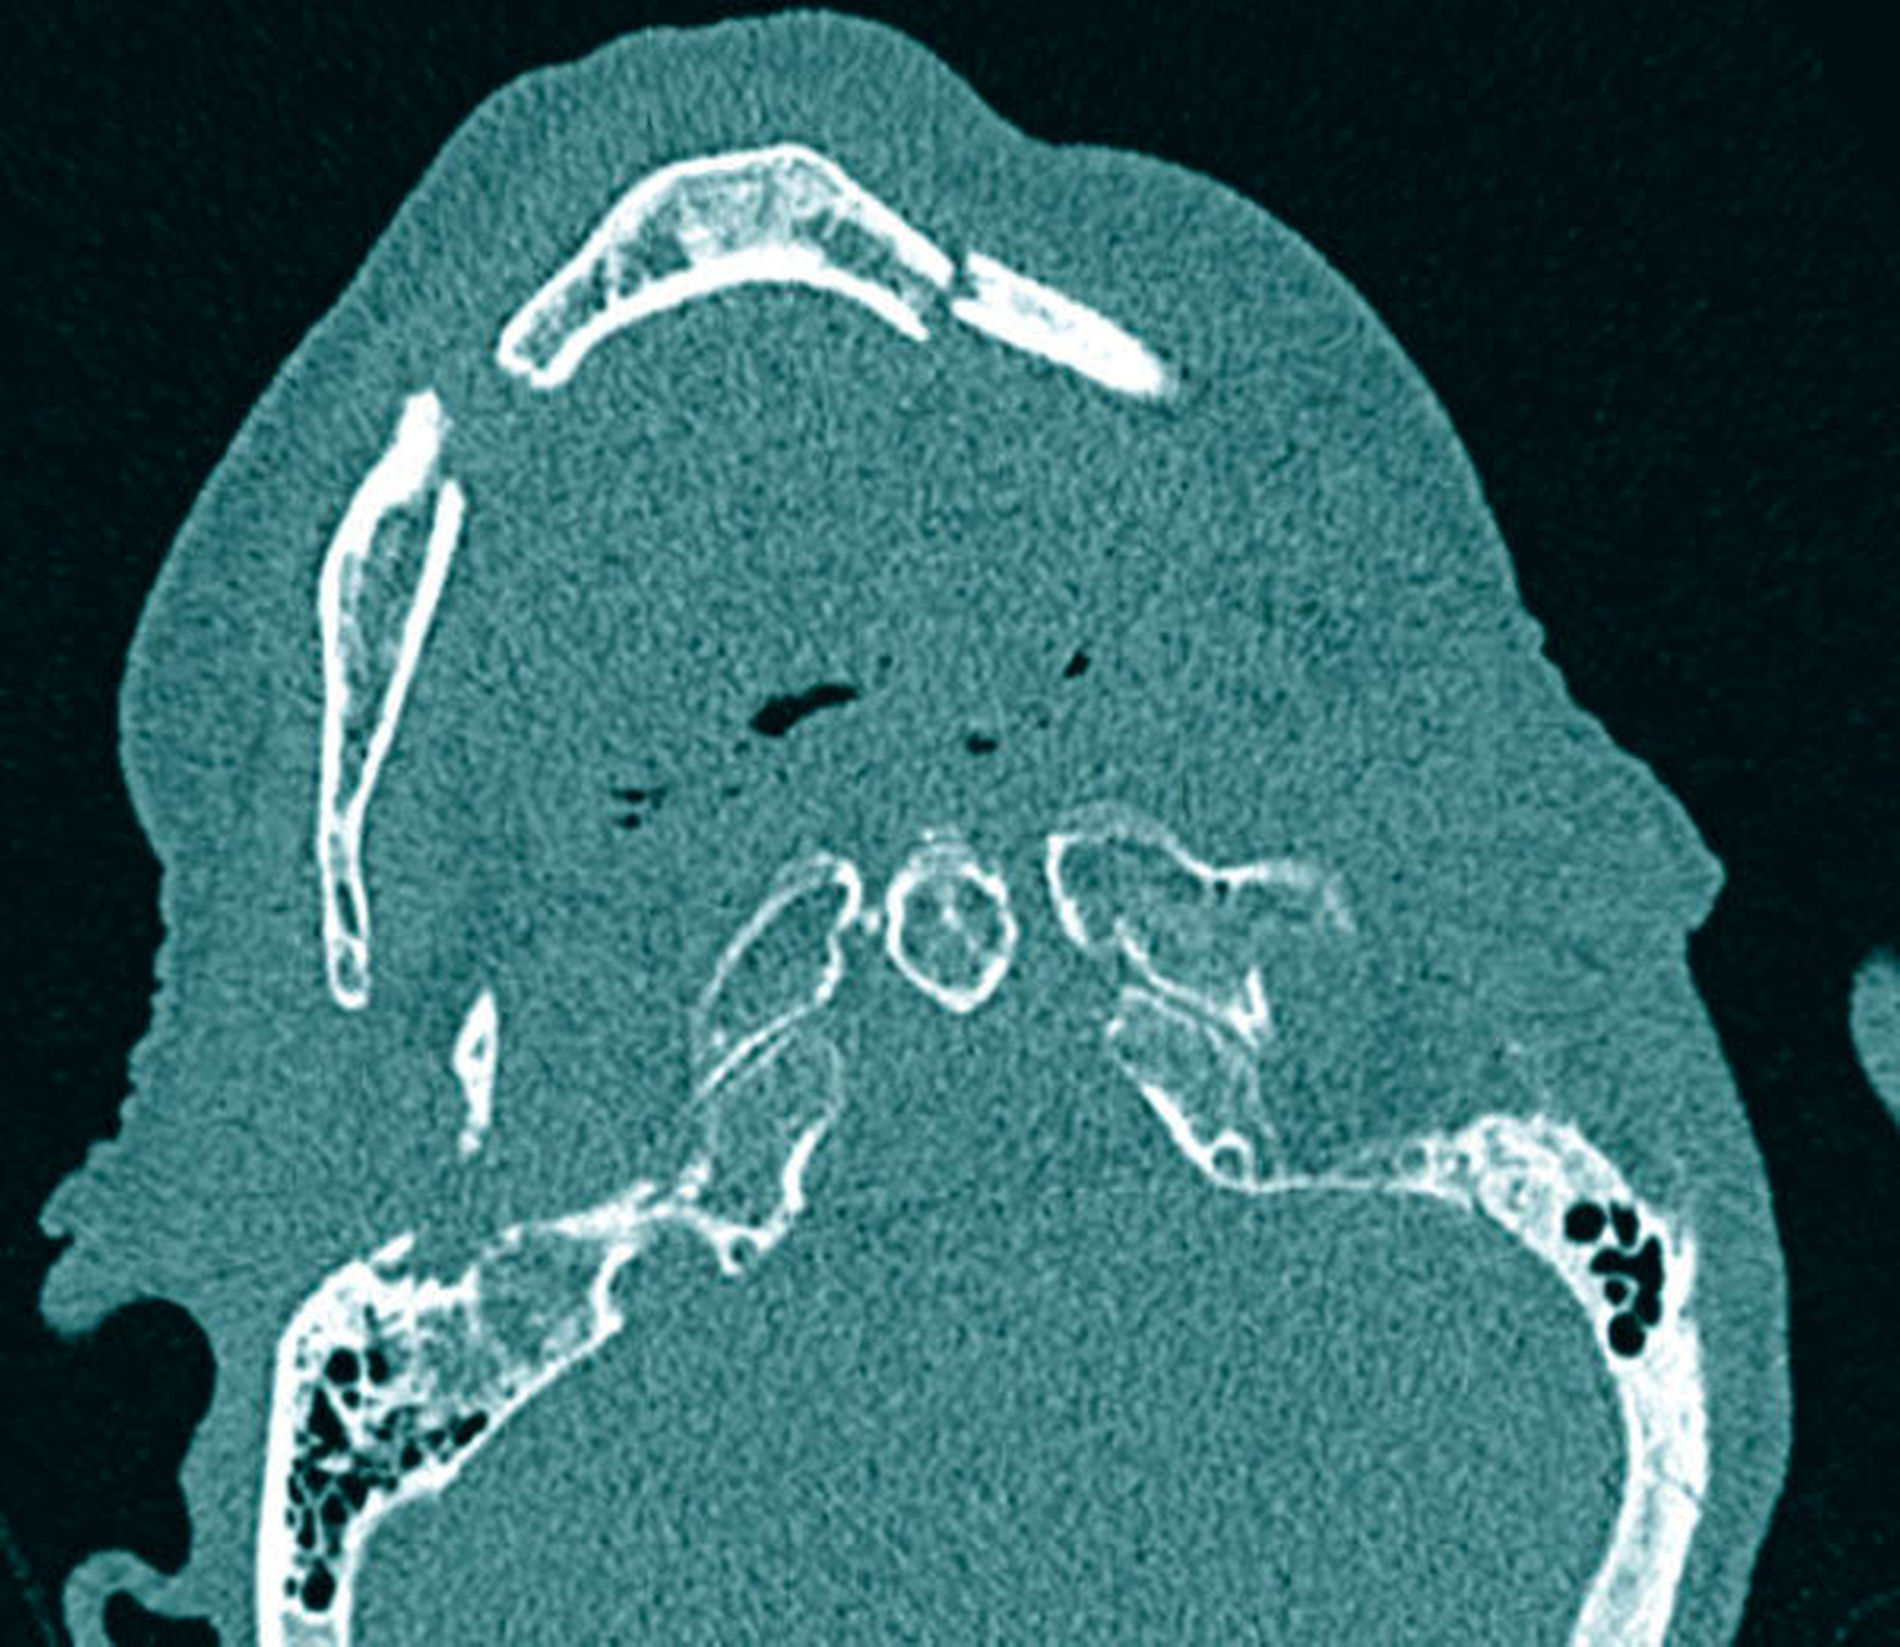

Die erste Sichtung erfolgte wegen des Verletzungsmusters und eines Glasgow-Coma-Scale-Score von 8 (einem Score-System zur Einschätzung des neurologischen Status zum Beispiel bei Schädel-Hirn-Trauma, Normalwert: 15) über die chirurgische Notaufnahme und die Abteilung für Neurochirurgie. Von neurochirurgischer Seite zeigte sich eine Subarachnoidalblutung ohne akuten Interventionsbedarf und eine nicht dislozierte Kalottenfraktur. Aufgrund einer zusätzlichen dislozierten Mehrfragmentfraktur des Unterkiefers (Abbildung 1) wurde die Abteilung für Mund-, Kiefer-, Gesichtschirurgie konsultiert.

Klinisch präsentierte sich die Patientin mit einer massiven Unterkieferrücklage (Abbildung 2) mit Rückfall der Zungenmuskulatur, mobilem Unterkieferfrontsegment sowie einem Mundboden- und einem Kinnhämatom. Die Kiefer waren komplett zahnlos und zeigten eine ausgeprägte Atrophie. Eine Prothese existierte nicht. Die Mundöffnung schien nicht eingeschränkt. Aufgrund der neurologischen Einschränkungen der Patientin war eine Untersuchung von Sensibilität oder Motorik nicht abschließend möglich. Bei der klinischen Untersuchung zeigte sich durch die Rücklage des anterioren Unterkiefers eine Verlegung der Atemwege mit Sättigungsabfällen bis 84 Prozent O2, die sich klinisch in einer Schnappatmung manifestierte. Bei manueller Reposition des Unterkiefers normalisierte sich die Atemfrequenz mit peripherer Sauerstoffsättigung bis 96 Prozent O2 (100% unter Sauerstoffgabe). Die manuelle Reposition wurde von einem knirschenden Geräusch begleitet (Krepitation).